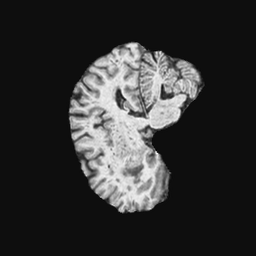

Exp. 2: Fetal brain data is used to test the robustness of our approach under real conditions. Fetuses younger than 30 weeks very often move a lot during examination. Fast MRI sequences allow artifact free acquisition of individual slices but motion between slices corrupts consistent 3D information. Fig. 3 shows that our method is able to accurately predict also under these conditions. For this experiment we use from three orthogonally overlapping stacks of ssFSE slices covering the fetal brain with approximately 20-30 slices each. We are ignoring the stack transformations relative to the scanner and treat each individually. For , 28 clinically approved motion compensated brain reconstructions are resampled into a volume with spacing. A density of 500 unique sampling normals has been chosen via the Fibonacci sphere sampling method with 25 sampling planes evenly spaced between -25 to +25 on the Z-axis. This gives a plane spacing of 2mm, sampling only the middle portion of the fetal brain. Training took approximately 10hrs for 30 epochs. Prediction, i.e., the forward pass through the network, takes approx. 12 ms/slice.

Here we show for Exp. 1, Exp. 2, and Exp. 3 randomly selected examples of images that have been presented to the network (ground truth) compared to an image sampled at the predicted location.

In these experiments, we present a ground truth (GT) image to the network to estimate the respective transformation parameters needed to reorient the slice in its correct world co-ordinates. Using the transformation parameters, we generated a slice from the 3D atlas in the location where the network has predicted that slice should be (denoted as SVRNet).

The slices are compared side-by-side to give a visual representation of “where the slice really is” and “where the network thinks the slice is”.

0..5.2 Exp. 2:

Slices, from a motion corrupted MRI stack, are segmented and cropped. Since there is no ground truth for the queried images, an arbitrary fetal atlas is used for visualization in Fig. 11 and 12.